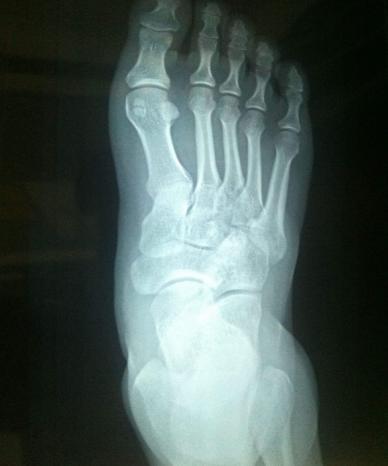

初步处理阶段:迅速叫人拿冰块或者冷水过来冷敷,用冰敷袋放置疼痛处,以降低发炎反应并可有效止痛。(此举的目的是冷却血液,让其凝固,崴脚之后血管肯定破裂,防止其出更多的血),想办法把伤足垫高,促使静脉回流,从而减轻肿胀和疼痛,并且减少受伤部位的活动度和对受伤处副韧带或肌肉的牵拉,以避免损伤的加重。确认没伤到骨头可以自行解决,伤到了还是乖乖去医院吧!!一般情况不会伤及骨头